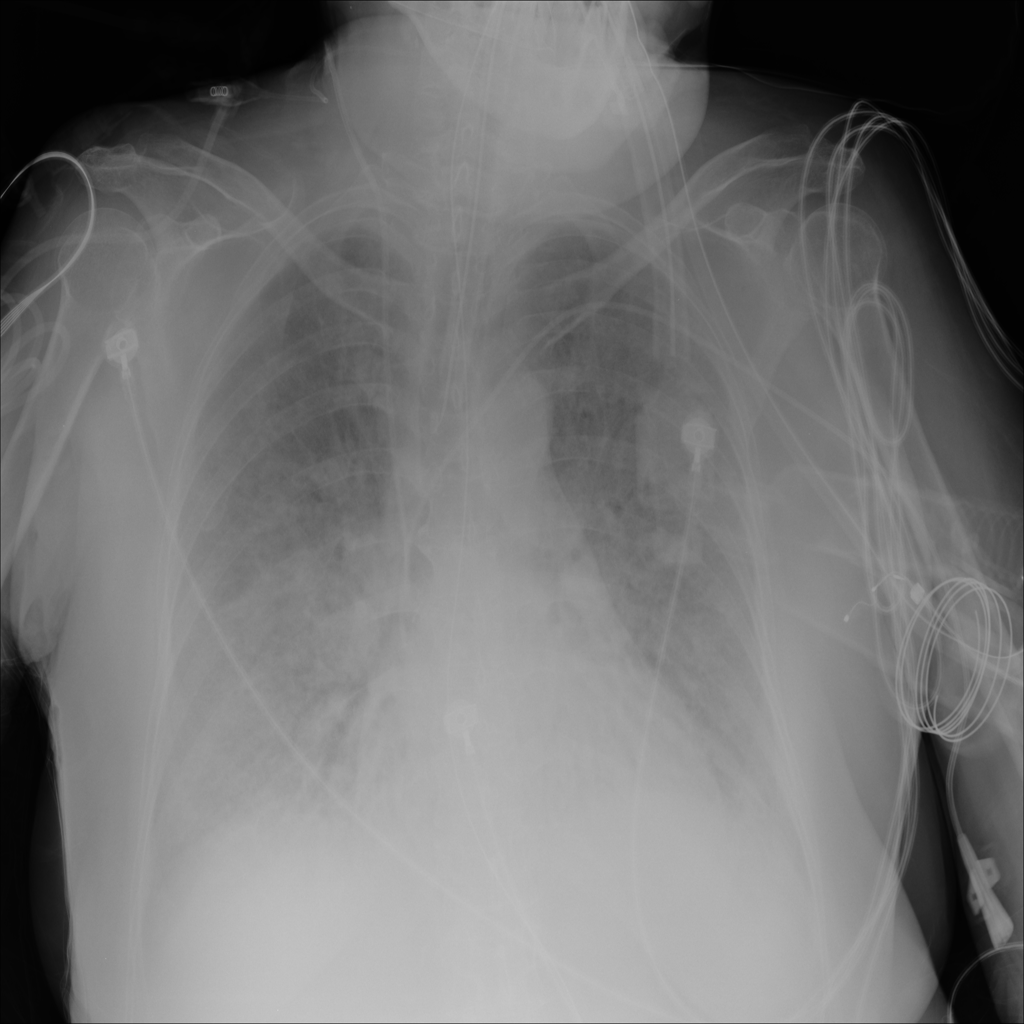

Consolidation

Consolidation refers to air-space filling that makes part of the lung appear denser on imaging.

Showing up to 90 reference images for Consolidation.